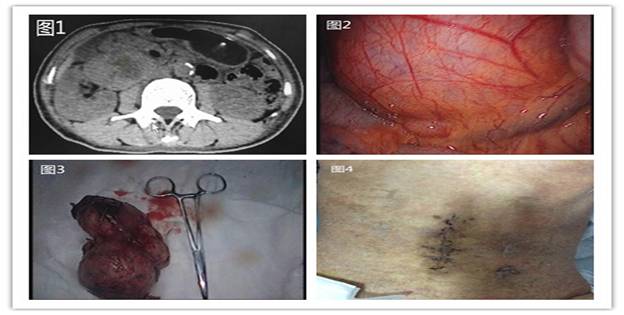

據(jù)悉,59歲的患者羅阿姨在7-8年前就已發(fā)現(xiàn)腹腔內一腫塊,當時僅“核桃”大小,因沒有任何不適,所以也就沒引起重視。直到近日,因“糖尿病、皮膚濕疹”入住我院內分泌科,查體顯示,右下腹可捫及一約6cm*5cm大小包塊,邊界清,無明顯壓痛,全腹CT檢查發(fā)現(xiàn)其右側中腹部可見一約11cm*6cm*6cm巨大混雜密度包塊,周圍臟器受壓明顯(圖1)。為求外科治療,轉入胃腸外科。經過仔細分析病例、閱片,發(fā)現(xiàn)該患者腹腔內的巨大腫瘤位于腹膜后,已累及腹腔重要血管、神經及臟器,手術難度較大。結合患者既往糖尿病多年,血糖控制差,若行傳統(tǒng)開腹手術,術后切口感染、愈合又是一難題;若不進行手術,巨大腫瘤將有繼續(xù)壓迫臟器、甚至破裂可能,以致威脅生命。為此,在譚曙光主任的帶領下,全科人員反復研究病例,考慮腹腔鏡手術具有創(chuàng)傷小、恢復快、鏡下視野清晰、安全可靠等優(yōu)點,決定行腹腔鏡微創(chuàng)手術。

術中探查發(fā)現(xiàn),腫塊位于右側結腸旁溝、右腎下極與十二指腸降部間隙(圖2)。由于腫塊較大,術中盡量游離周圍臟器、血管,進而形成“圍攻式”完整剝離腫塊,術中失血約20ml。經過約2個小時的努力,埋在患者體內的這枚“定時炸彈”被順利摘除(圖3)。術后患者腹部切口愈合良好(圖4)。